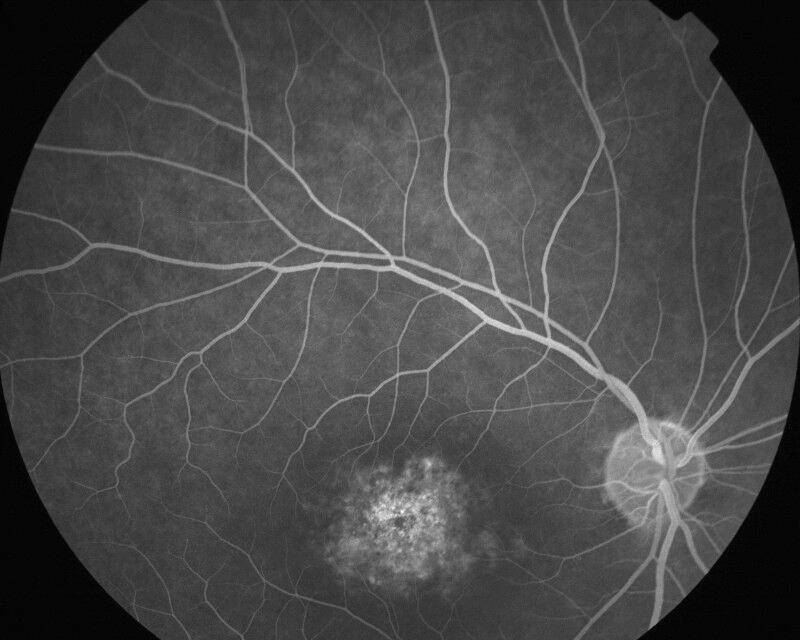

DYSTROPHIE DES CONES